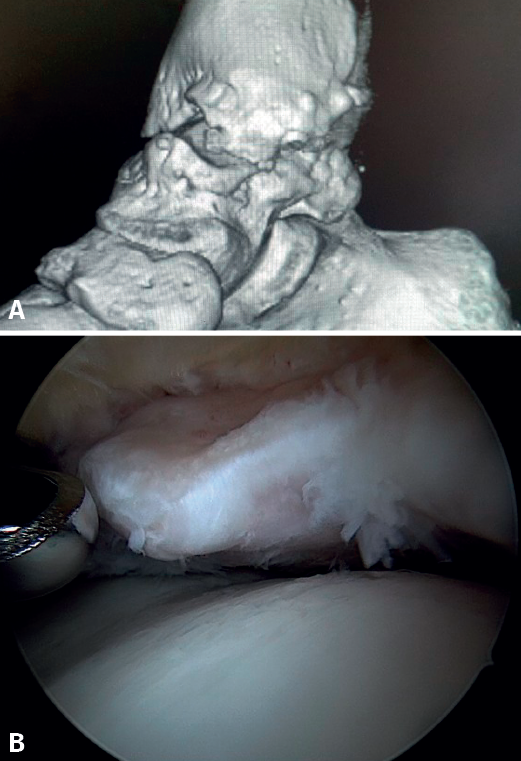

Bony AAI due to osteophytes has also been linked to the presence of chronic instability. It has been postulated that altered joint kinematics secondary to ligament insufficiency favors the development of osteophytes in the anterior region of the tibia and talus(36,37). Recent studies have questioned the theory of repeated capsular traction as the origin of osteophytes in sports(38), as it is easily demonstrated that osteophytes are located intra-articular within the capsular insertion, in the context of ankle arthroscopy (Figure 2). Therefore, ankle dorsiflexion arthroscopy is essential to safely resect osteophytes without damage to the capsule or overlying structures, whereas the classical traction technique (invasive or otherwise) would make resection extremely difficult, and is thus not recommended nowadays for routine use(3,39). Vega distinguished between two types of osteophytes(3), according to whether they are caused by repetitive trauma (peak-shaped) or instability (visor-shaped). The concept of micro-instability is associated with repetitive micro-trauma, which could be the origin of osteophytes with this characteristic morphology (Figure 3).

Figure 3. Osteophyte due to chronic instability. A: the osteophyte forms a bone block extending over the anterior margin of the tibial plafond and the anterior aspect of the medial malleolus; B: arthroscopic view.